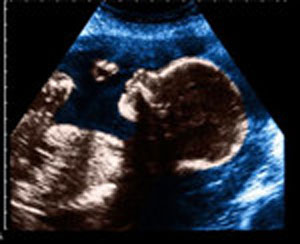

Chinese scientists have improved key

components in Magnetic Resonance Imaging (MRI) equipment, creating clearer

fetal imaging.

MRI is an important tool for discovering

complex congenital diseases during fetal development. It is especially useful

in the diagnosis of neurodevelopmental abnormalities and cardiovascular

diseases.